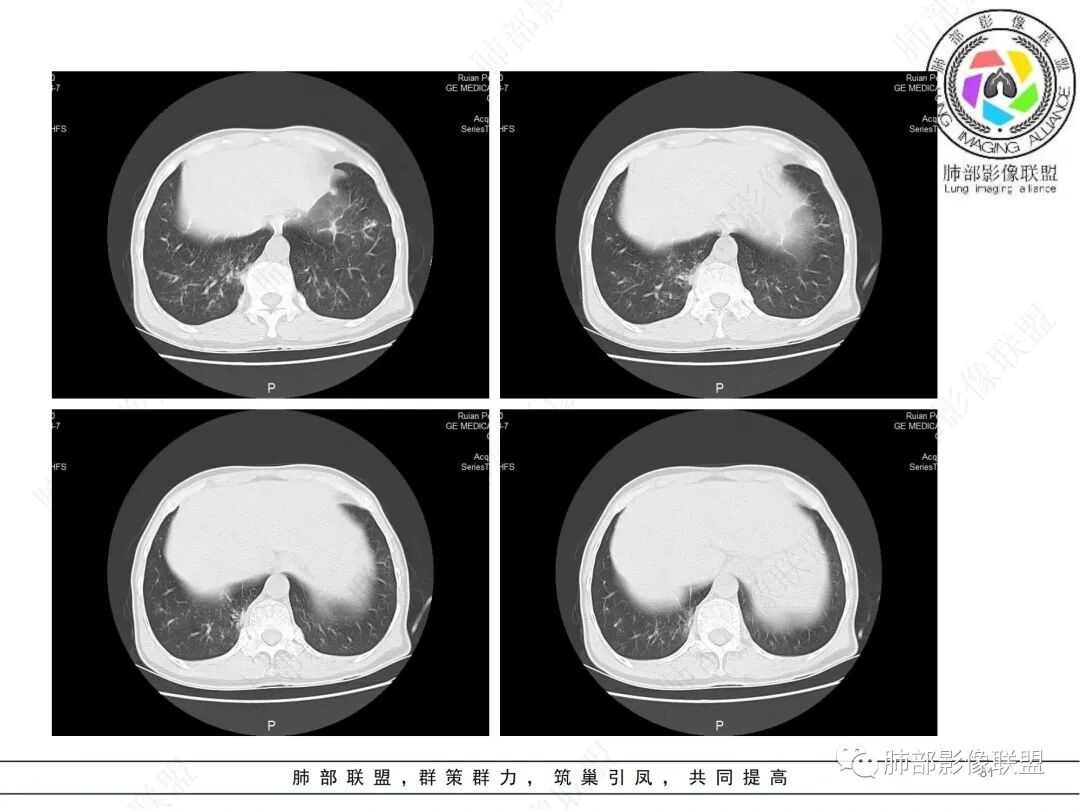

58岁男性,咳嗽胸闷3天,咳较多褐粘液痰,无发热。有2型糖尿病病史。白细胞与中性粒细胞升高。CRP升高。鳞状上皮细胞癌抗原轻度升高。结核T细胞免疫斑点实性阳性。肺炎支原体、衣原体IgG轻度升高。支气管镜显示支气管炎性改变、右肺下叶背段管腔狭窄。2.影像特点:

2022.6.24CT显示两肺弥漫性段、亚段支气管壁增厚(两肺各叶都累及),增厚的支气管壁外可见沿着支气管分布的渗出、实变影。另外远端肺内亦可见多发树芽影、结节影,其边界欠清晰。右肺下叶基底段局部胸膜下亦可见小斑片影,边界不清。2022.6.27CT显示两肺增厚的支气管壁外的渗出实变影明显增多、范围更广。远端肺内病灶亦增多、范围增大。部分位于胸膜下的病灶可见侧向融合趋势。3.病例分析: